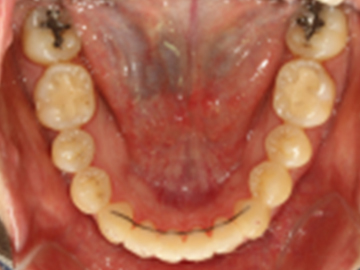

고정식 유지장치를 이용해 교정치료 후 재발을 방지합니다.

가철식 유지장치를 이용해 교정치료 후 재발을 방지합니다.

교정치료 후 일어나는 약간의 재발은 자연스러운 현상 중 하나입니다.

치아와 턱이 생리적으로 가장 편안한 상태를 찾아가면서 일어나기 때문입니다.

하지만, 힘들게 한 교정치료 결과가 다시 예전으로 돌아가는 것은 막아야겠죠!

심다치과에서는 교정치료 후, 위아래 유지장치를 통해 재발이 최소화되고자 합니다.